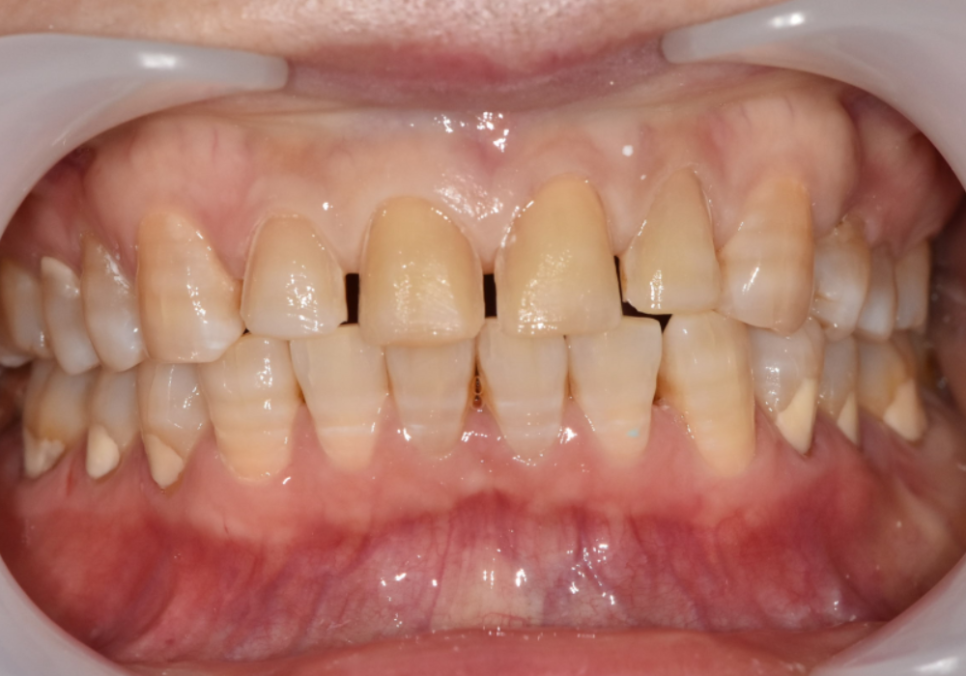

얼마 전에 내원하신 한 환자분이 특히 기억에 남습니다.

앞니가 벌어져 있고,

갈색 가로줄이 선명하게 보여서 웃을 때마다

입을 가리게 된다고 하셨습니다.

자세히 보니 전형적인 항생제 변색이었습니다.

대신, 라미네이트로 치아 벌어짐과 변색을

동시에 해결하는 것이 가장 효과적이라고 설명드렸습니다.

환자분도 오랜 고민 끝에 결정하셨고,

웃을 때 가장 잘보이는

앞니 4개를 라미네이트로 진행했습니다.